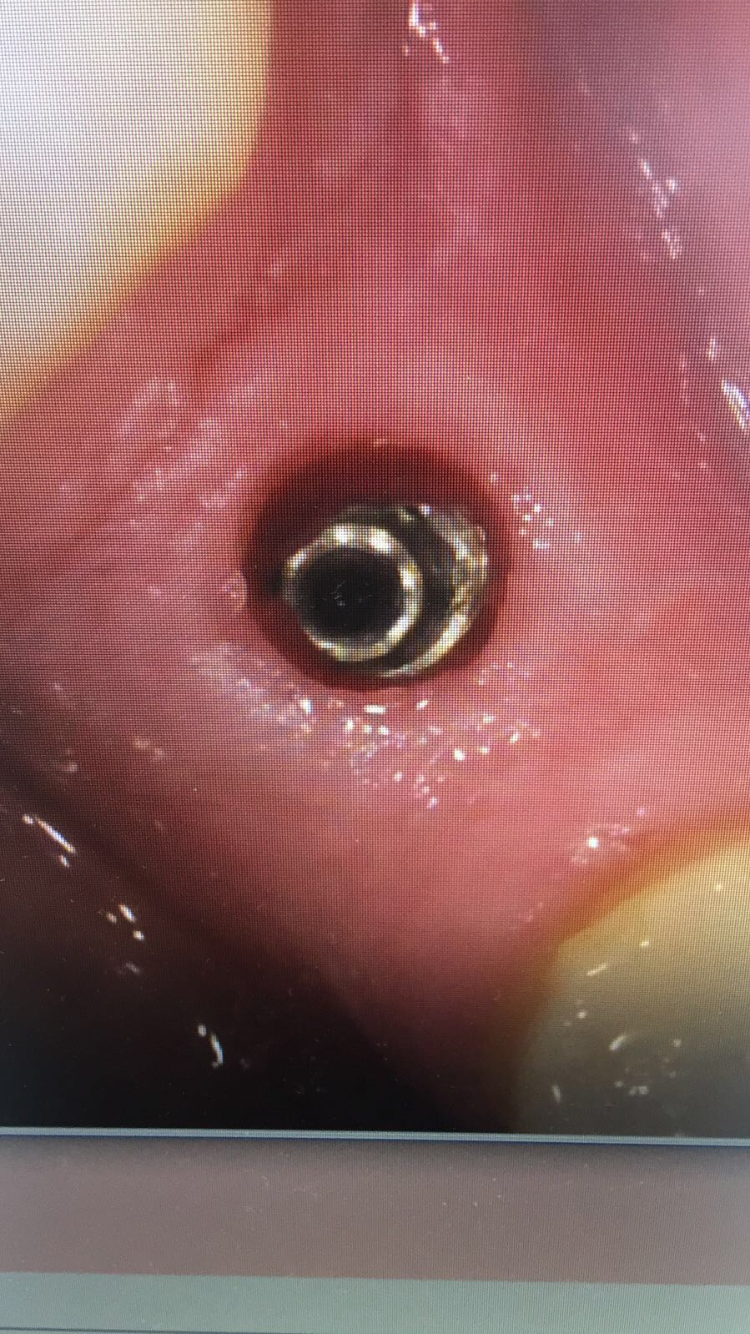

Me llego esta paciente con este implante q es una conexión cónica y después va el hexágono ,,, no tiene ninguna información del implante y manifiesta que se lo coloraron [...]